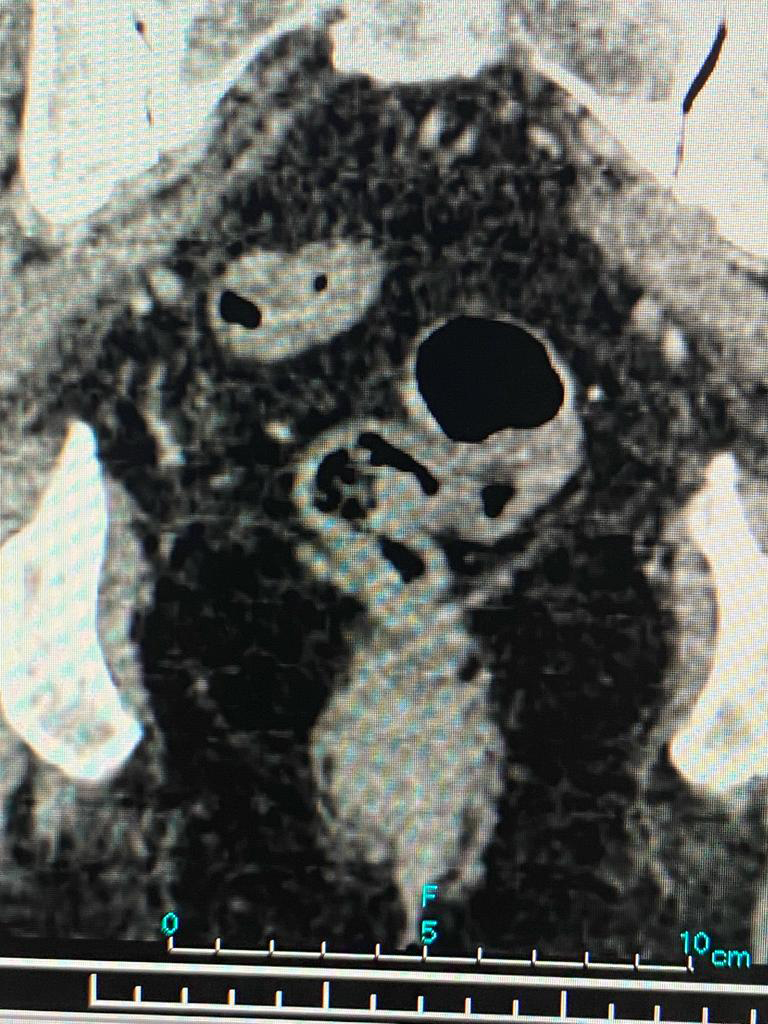

After admission, we reviewed the history, investigations, sequence of events and old CT scan. We suspected colonic diverticulosis with perforation as the original reason for sepsis. We repeated the CT scan of abdomen and pelvis which showed a pelvic abscess along with a sigmoid colonic diverticular phlegmon confirming diverticular perforation. The drain placed during previous laparoscopy was out of position. After a multidisciplinary meeting, treatment plan was charted out. The original drain was used to guide another drain deep in the pelvic abscess cavity under radiological guidance thus ensuring free drainage. The antibiotics were adjusted based on culture sensitivity of the intraabdominal pus. There were multiple highly resistant organisms and very few antibiotics were available for treatment. Hence the definitive surgery was deferred. Patient recovered and was sent home on intravenous antibiotics and drainage catheter.